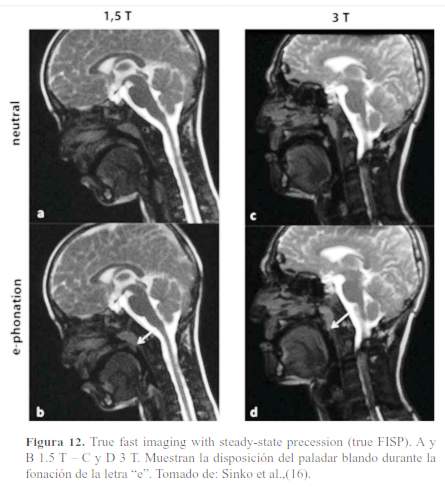

En la respiración tranquila y en la pronunciación de sonidos como la “m” y la “l”, el velo del paladar se relaja. Cuando se le ordena al paciente a decir “a” se produce un ensanchamiento del istmo de las fauces y se hace más visible la porción oral de la faringe(12,13,14). Así mismo, durante la fonación de la “e” el velo del paladar se mueve hacia arriba, hacia la pared faríngea (figura 12) (15). La parálisis de los músculos del velo del paladar da lugar a una regurgitación del alimento hacia la cavidad nasal y una pronunciación nasal de las palabras (8,16).

El conocimiento de las funciones de los músculos del paladar blando se puede realizar como hemos visto en tiempo real mediante secuencias rápidas de resonancia magnética. En el estudio de Sinko et al., estudiaron 65 imágenes por resonancia magnética en 1,5 y 3 teslas en secuencia de estado estacionario steady-state precession (trueFISP) de pacientes con historia de paladar hendido, evaluando las estructuras anatómicas en tres estados funcionales (reposo, fonación de la vocal “e” y fonación de la letra “k”). Observaron que la calidad de imagen fue mucho más alta en 1,5 tesla que, en 3 teslas, además demostraron que para una mejor evaluación de las estructuras del velo del paladar (en los tres estados funcionales) es mejor usar la imagen de 1,5 tesla (18).Adicionalmente, se podría pensar que la posición decúbito supino durante el examen por resonancia magnética pueda alterar las estructuras del velo del paladar, sin embargo, Perry JL demostró que la posición del cuerpo vertical tuvo un efecto mínimo sobre el espesor, longitud y altura del velo del paladar. Por lo que podemos deducir que la posición decúbito supino no altera o no ejerce un efecto desfavorable para el diagnóstico imagenológico (32).